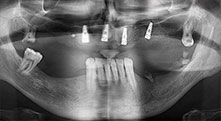

Bratu: We routinely use the instruments for harvesting bone blocks and splitting alveolar ridges. We also use the Piezomed B6/B7 for osteotomy of impacted teeth and removing failed implants. All indications that require deep, clean cuts.

Could you describe briefly, for example, your procedure for mobilizing bone blocks for transplantation?

Bratu: We prefer to harvest bone from the external oblique ridge of the posterior mandible, not from the interforaminal region. After the soft-tissue incision, we use the new saws to define the amount of bone to harvest. With this approach, we also use them for the entire preparation in almost 80% of cases. We may also use other piezo instruments and then at the end a chisel to mobilize the block. We find that this is a very effective surgical technique.

Bratu: We like to use the sandwich technique for augmentation in the lateral mandible. A bone cover is prepared with the piezo saw and the crestal fragment is fixed with microscrews. We place a mixture of autologous bone and xenogenic bone replacement material in between. This works very reliably. You should always ensure sufficiently dimensioned vertical cuts when splitting the alveolar ridge in the mandible. Otherwise the bone may fracture easily.